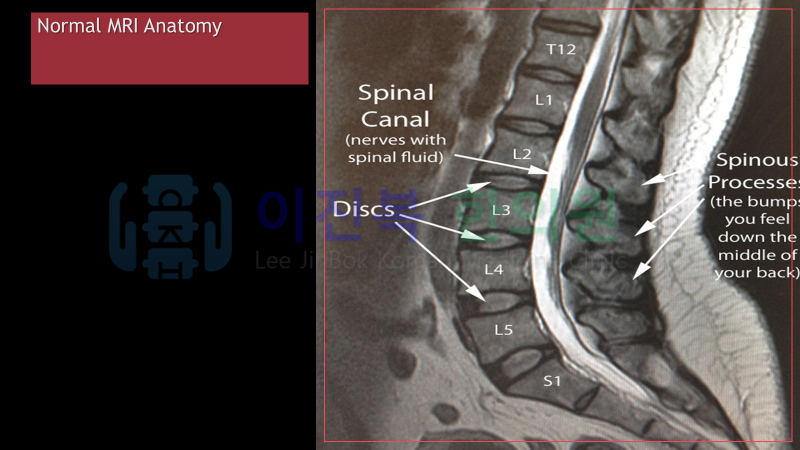

오늘은 척추관 협착증에 대해 알아보겠습니다.